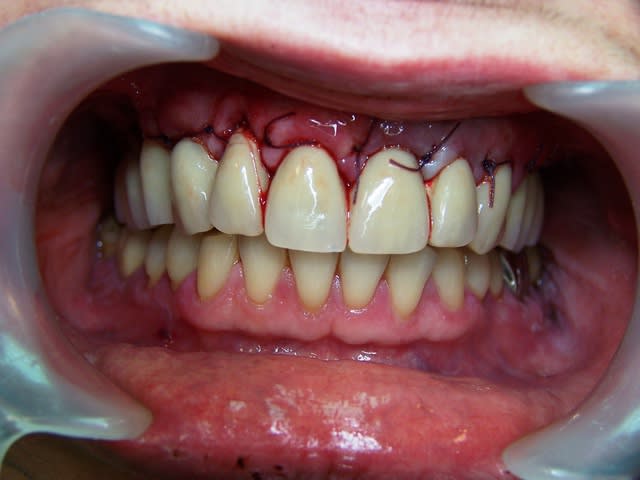

sympa l'aspect gingival sur la dernière photo de la prothèse en place avec les écarteurs

Il y a quelques années que je présente des cas de bridges provisoires fixes sans ciment, juste maintenus par friction. Ci-joint après quelques mois de port du provisoire photo de la cicatrisation gingivale, OTP, biscuit céramique réalisé par le prothésiste de béotien.

(patiente édentée total portant une PCA)